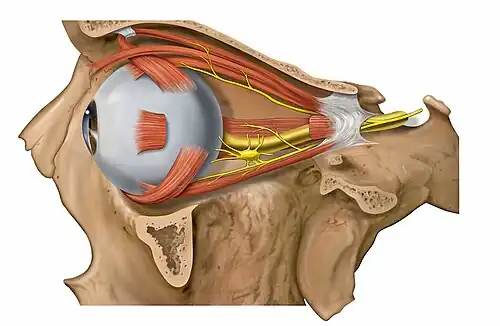

Extraocular muscles

Each eye has seven extraocular muscles located in its orbit.[7] Six of these muscles control the eye movements, the seventh controls the movement of the upper eyelid. The six muscles are four recti muscles: the lateral rectus, the medial rectus, the inferior rectus, and the superior rectus; and two oblique muscles: the inferior oblique, and the superior oblique. The seventh muscle is the levator palpebrae superioris muscle. When the muscles exert different tensions, a torque is exerted on the globe that causes it to turn, in almost pure rotation, with only about one millimeter of translation.[8] Thus, the eye can be considered as undergoing rotations about a single point in the centre of the eye.

Image showing orbita with eye and nerves visible (periocular fat removed)

Image showing orbita with eye and nerves visible (periocular fat removed) -

Image showing orbita with eye and periocular fat

Image showing orbita with eye and periocular fat -